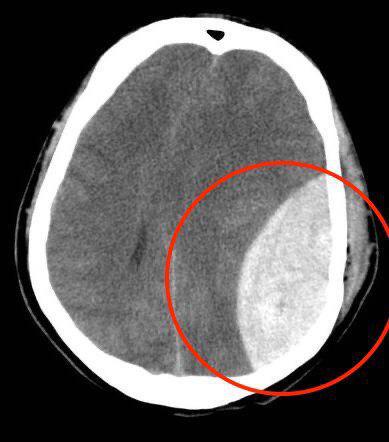

醫護人員證明 青年被港警打至腦出血 6小時後才送醫

紅圈為血塊。(反送中已核實資訊頻道)

【新唐人亞太台 2019 年 10 月 09 日訊】香港有醫護人員透露,一名青年抗議,遭警方以警棍毆打頭部致顱內出血,拖延6小時後才送醫,如再延遲傷者恐成植物人,甚至可能死亡。

據香港「反送中已核實資訊頻道」週二(10月8日)消息,有醫護向該頻道提供警方濫暴情況。醫護人員披露一名7日晚送院的青年示威者遭警方以警棍毆打頭部,導致顱內出血,血塊占腦部相當大面積,需要立刻手術取出血塊。

醫護人員指,青年從被打傷至送院,警方拖延了6小時才送醫,若再耽誤,傷者恐成植物人,甚至可能死亡。傷者現時在屯門醫院重症治療部留醫,仍未完全清醒。

這位醫護人員還提供了傷者的腦部掃描示意圖,紅圈為血塊。